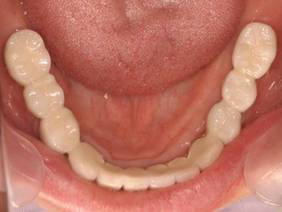

上顎

下顎

上部構造装着後6年。ハイブリッドレジンを使用したため、少し艶がなくなってきました。上部構造の材料には金属、ハイブリッドレジン、セラミックなどがあります。セラミックはきれいですが欠けやすいため、最近はフルジルコニアを使っています。

上顎 少しすり減ってきました。

下顎。12か月に一度メインテナンスをしています。

治療終了後11年

咬耗するのでコンポジットレジンで盛り上げています

ほとんど変化ありません